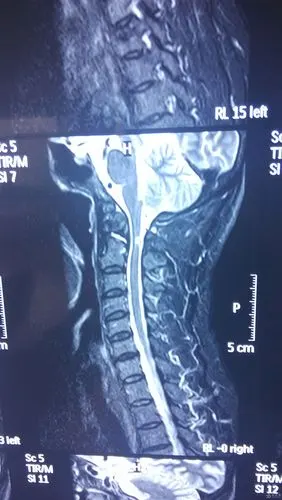

脊髓型颈椎病术前ct片脊髓型颈椎病术前x线正,侧位片患者为42岁男性

请大神们看个颈椎病的片子

颈椎ct:后纵韧带钙化.该患者同样有手术指征.